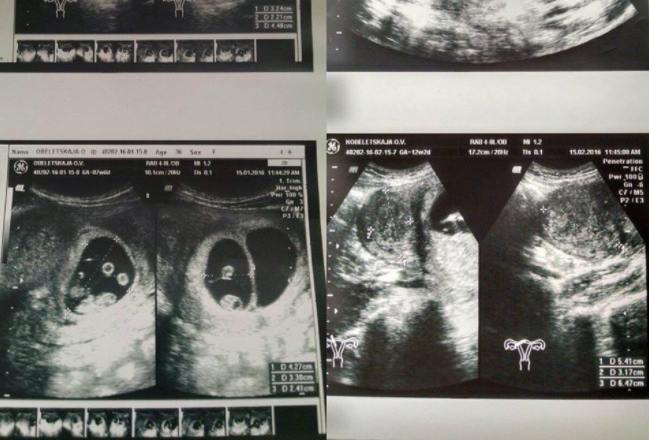

She eventually went to the doctor for an ultrasound. There it was confirmed that she really was not expecting twins. The truth was much more shocking for the doctors and the parents.

Oksana was expecting quintuplets. The shocked mother realized that all her plans were changing. The doctor ran to share the joyful news with the entire hospital staff, who of course had never encountered anything like it before.